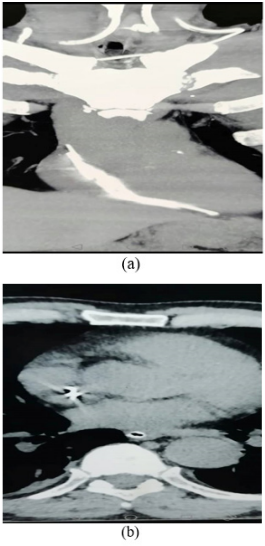

A 61-years old man with a medical history of diabetes mellitus and hypertension followed for T3N0M0 laryngeal cancer was admitted to our department of head and neck surgery for surgical management after the failure of conservative treatment. The patient had previously received 2 cycles of Docetaxel-cisplatin-5-fluorouracil-based chemotherapy and was judged a bad responder. The port catheter was kept in place thinking the patient might need additional chemotherapy cycles. A total laryngectomy with bilateral neck dissection was performed. Intraoperatively, when moving the catheter during neck dissection, the device fractured and the distal part migrated in the internal jugular vein. Digital palpation of the vessel didn’t identify any foreign body. The operation was carefully carried on after contacting radiologists for a prompt CT scan immediately after surgery. Postoperative radiological findings showed the distal part of the catheter budging in the right cardiac cavities (Figure 1).

Figure 1 Thoracic CT scan coronal (a) and axial (b) sections showing the distal part of the catheter bulging in the right cardiac chambers.

The patient was transferred to an interventional cardiology unit where the foreign body was retrieved using femoral venous access (Figure 2). Postoperative follow-up was uneventful. The patient was discharged 12 days after surgery.